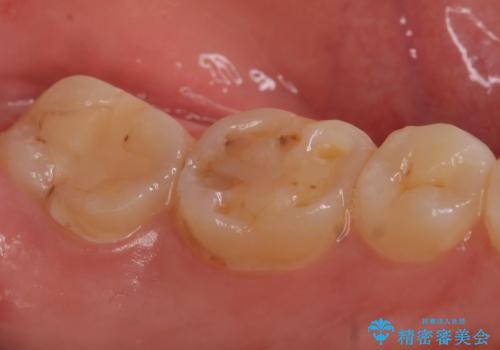

- 冷たいものを飲むと、左下奥歯がしみると来院された方の症例です。

検査の結果左下6が虫歯になっていたため、セラミックインレーによる修復を行いました。